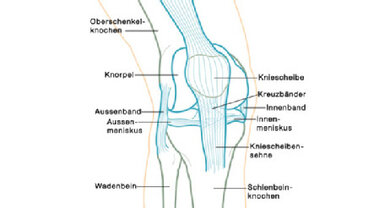

Übersicht über die verschiedenen Strukturen im Knie

Das Kniegelenk wird durch mehrere Bandstrukturen stabilisiert: das Außenband, das Innenband, das vordere und das hintere Kreuzband. Vor allem bei Sportunfällen können diese Bandstrukturen stark überdehnt werden und teilweise oder ganz reißen (Bänderriss, Bandruptur). Es kann nur zum Einriss eines einzelnen Bandes kommen (isolierte Ruptur), häufig sind aber mehrere Strukturen betroffen, es findet sich dann auch oft eine Meniskusverletzung. Insbesondere Sportarten mit einem fixierten Fuß wie Skifahren oder Fußballspielen mit Stollenschuhen stellen ein erhöhtes Risiko dar.